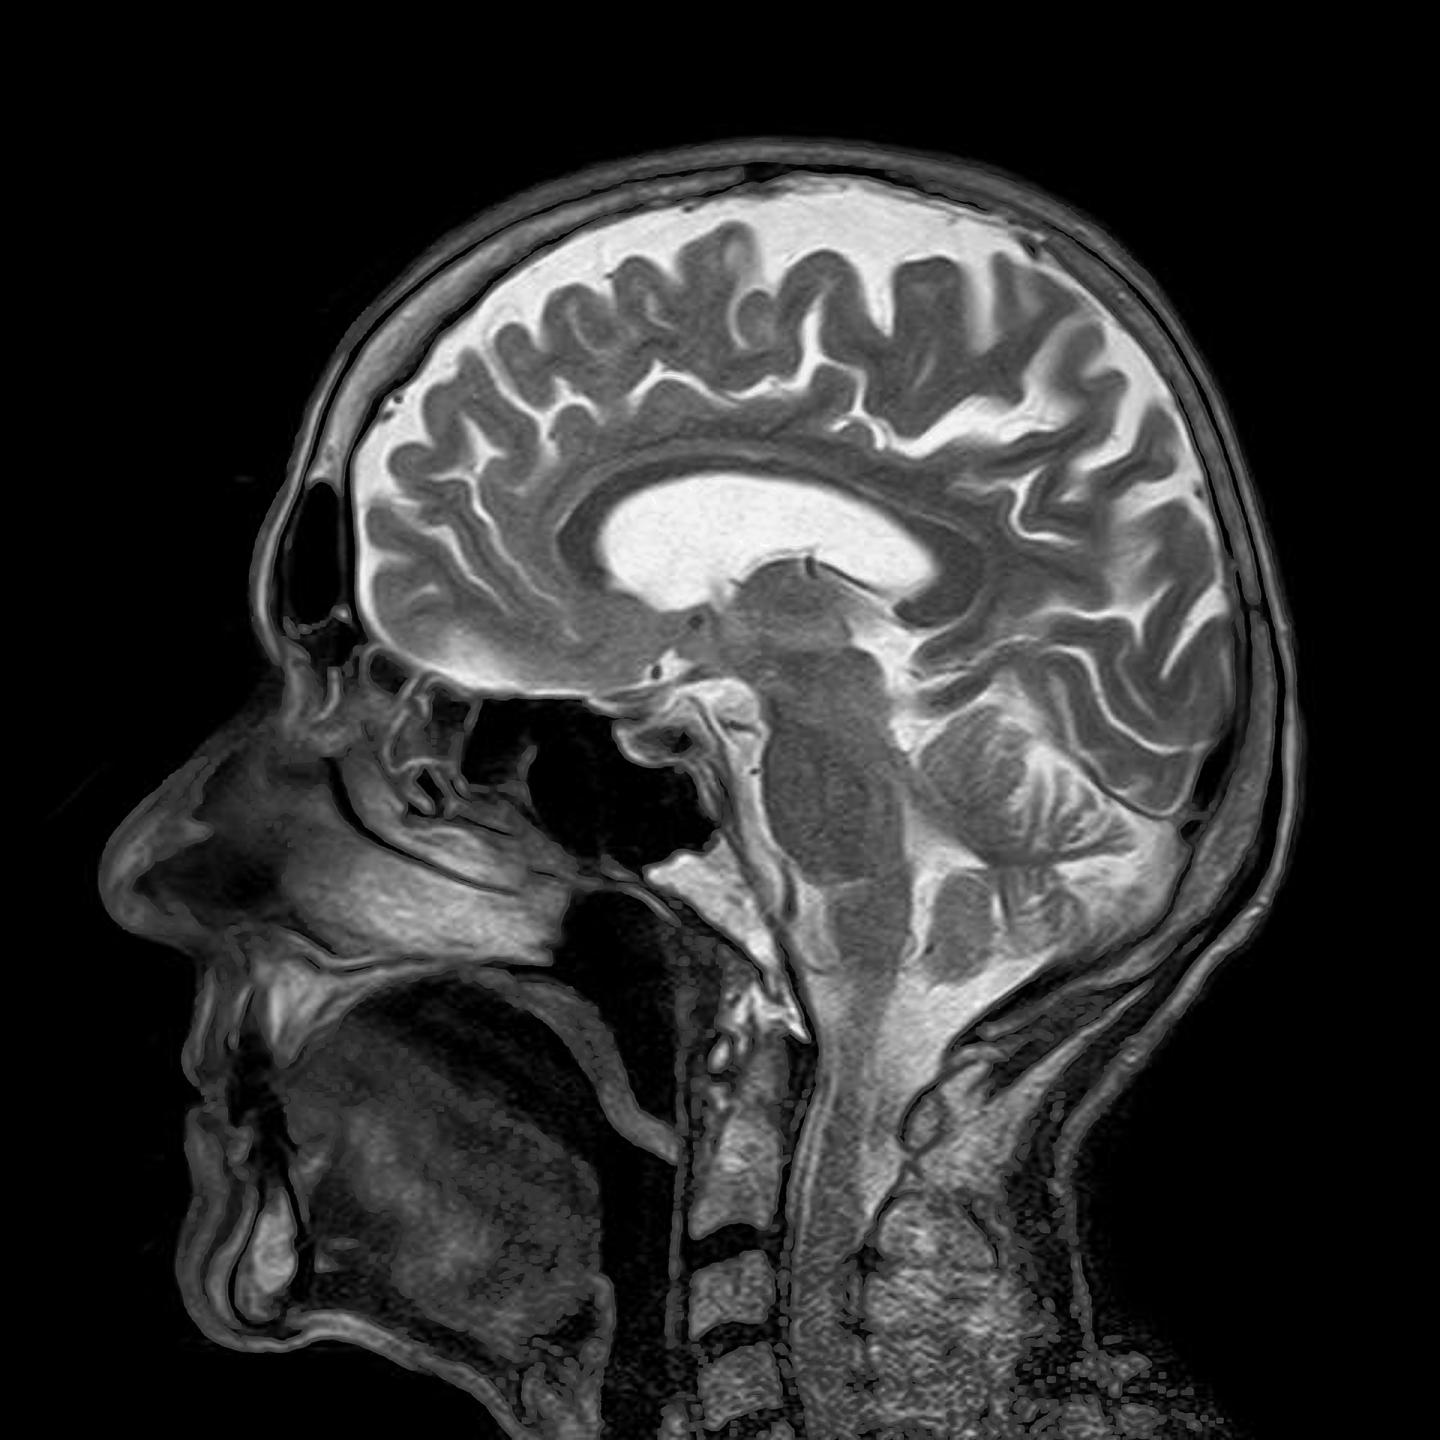

image: Scientists from Japan and the United States have identified a new mechanism of blood-brain barrier degradation in the post-stroke brain, involving acrolein-induced modifications of proheparanase. This discovery could lead to the production of newer and more effective drugs for stroke-related disorders.

The BBB is a structure located around the brain, which prevents the entry of unnecessary circulating cells and biomolecules into the brain. The blood vessels in the BBB are coated with a distinct and protective layer of sugar, called the endothelial glycocalyx, which prevents their entry. However, in the event of a stroke, which results in the blockage or severance of blood vessels in the brain, studies have shown that this glycocalyx and, in turn, the integrity of the BBB, get compromised. In addition, damage to the blood vessels leads to neuronal death and the build-up of toxic byproducts like acrolein.